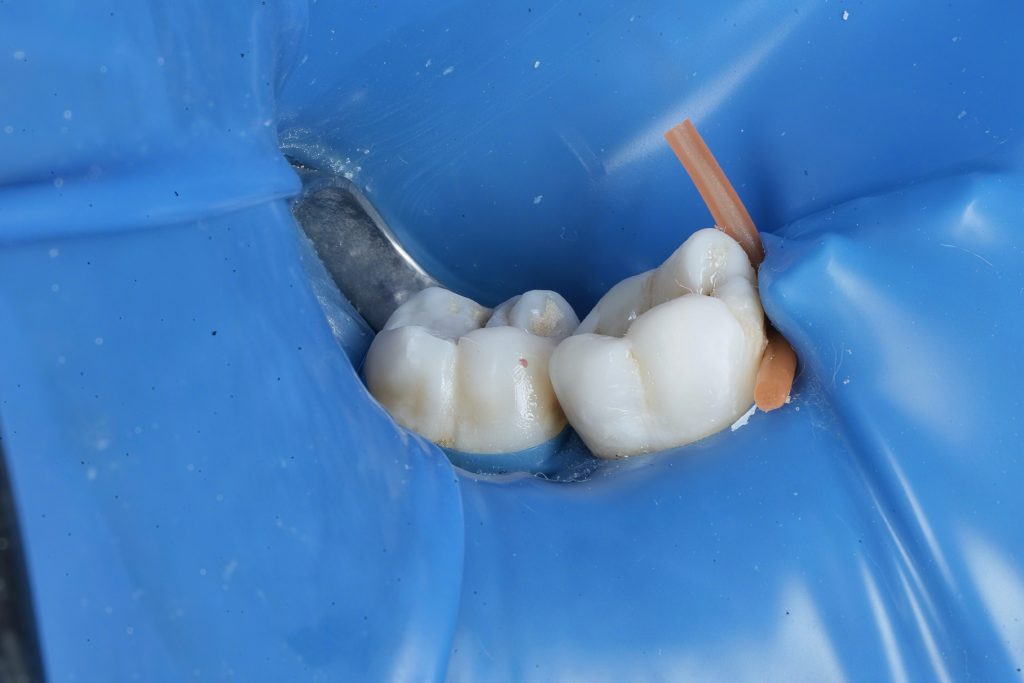

6️⃣ Class II Proximal Reinforcement

The proximal defect was restored immediately post-obturation.

- Garrison sectional matrix system used for tight proximal contact and contour (Fig 6).

- GC EverX Flow placed as the first 1–2 mm layer to reinforce weakened dentin.

- Incremental build-up completed with Tokuyama Estelite Sigma Quick (A2).

- Fig 6: Class II build-up using Garrison matrix + GC EverX Flow.